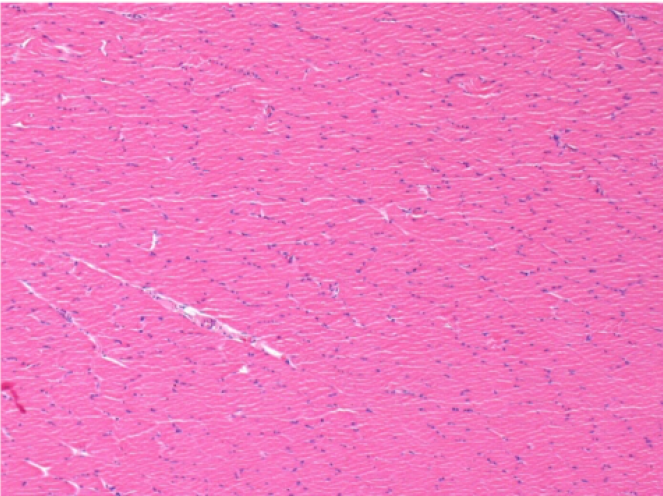

3 months (D90)after Endopeel Injection 0.1ml in the right pretibial muscle.

7 months (D210)after Endopeel IM Injection 0.1ml in the right pretibial muscle.

Complete Restitutio ad integrum after 7 months